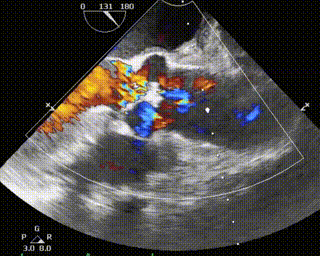

术前、术后超声对比

本次手术植入瓣膜定位准确,操作简便,症状即刻改善。术后超声显示瓣口未见明显反流,微量瓣周漏,主动脉瓣前向血流加速Vmax=1.9m/s,有效开口面积2.9cm²,PGmean=8mmHg。患者生命体征稳定,手术室当场清醒,手术圆满成功。术后复查超声恢复良好,3天后出院。